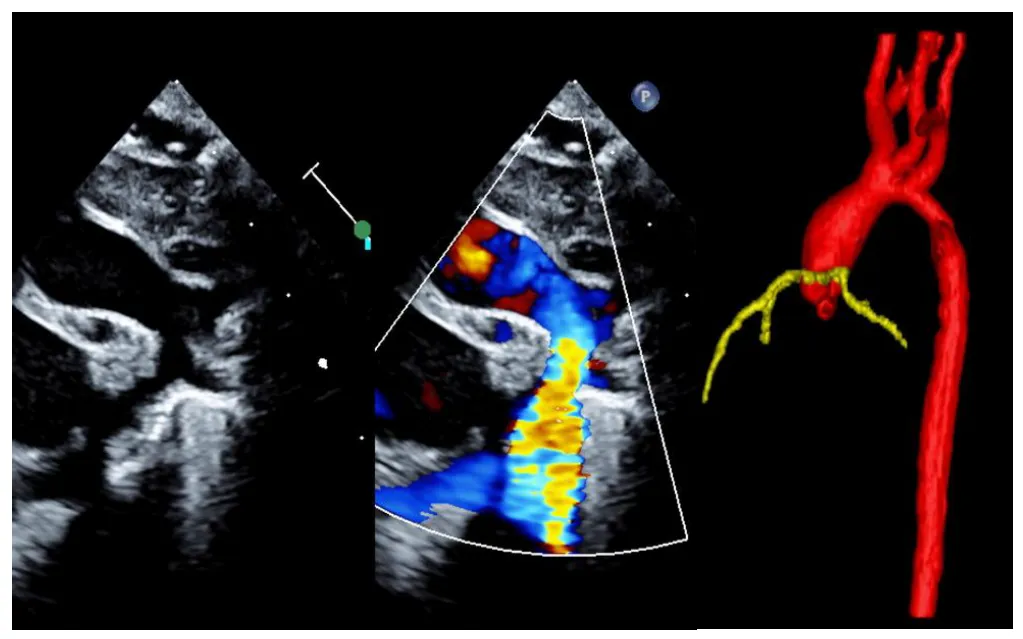

Figure 1. Diagnostic image of a newborn with coarctation as seen on sagital plane transthoracic echocardiogram (2D and color Doppler imaging) and CT angiogram (3D reconstruction).

A total of 121 patients were diagnosed with isolated coarctation of the aorta or arch hypoplasia over the ten-year study period. Of these, 7 patients did not require any intervention, and additionally 9 patients underwent transcatheter aortic angioplasty as their prior intervention and were therefore excluded. A total of 105 patients underwent surgical repair during the first year of life. Surgical techniques included coarctation excision with end-to-end anastomosis, extended end-to-end anastomosis/aortic arch advancement, and aortic arch augmentation with bovine pericardium patch. No patients underwent subclavian flap technique. During the post-operative period, 11 patients (10%) experienced one or more SAEs, which included chylothorax (N = 8), vocal cord palsy (N = 6), diaphragm palsy (N = 1), right diaphragm eventration (N = 1), severe subglottic stenosis (N = 1), acute kidney injury (N = 2) and necrotizing enterocolitis (N = 1) in the post-operative period. Table 1 compares the preoperative and operative characteristics of the study groups. Patients in the SAE group were more likely to have a known genetic anomaly (p = 0.0001) or had undergone a median sternotomy approach/complex arch repair (i.e., requiring patching of the aorta) (p = 0.0001). Turner syndrome (45 XO) was the most common genetic anomaly (3/3 patients in the SAE group, 2/7 patients in the non-SAE group). Other genetic abnormalities included Trisomy 21, Kabuki syndrome, and variants of uncertain significance (i.e., microdeletions or duplications). Interestingly, those with a prenatal diagnosis of coarctation had higher risk for SAE (p = 0.03), On multi-variate binary logistic regression analysis, genetic anomaly was the only independent predictor of SAE in the post-operative period (adjusted Odds Ratio = 6.8) (p = 0.04, 95% CL = 1.1 to 43). Factors which did not appear to be related to a SAE included ethnicity, age at diagnosis, birth weight, coarctation type (short or long segment), use of pre-operative advanced cross-sectional imaging for surgical guidance (Figure 1), age at surgery, or mean aortic cross clamp time.

We reviewed all patients diagnosed with simple coarctation of aorta who underwent surgical repair in infancy at our institute over a 10-year period (N = 105). Overall, most patients (~90%) had excellent immediate post-surgical outcomes. Patients with Turner Syndrome and those requiring median sternotomy surgical approach (for reasons such as long segment coarctation/complex arch repair or poor preoperative clinical status) appeared to be at a higher risk for post-operative morbidity based on our univariate analysis. Follow up of this cohort showed that they continued to have an excellent prognosis for survival free of reintervention (>96%). This data may be helpful for patient counselling and management of neonatal coarctation. In a study of 133 patients with simple coarctation repair by Minotti et al. [3], about 7% of patients had significant postoperative complications (heart failure, respiratory failure, infection/sepsis, arrhythmia, renal failure, pulmonary hypertension, and other), however only 2% of patients in their cohort required a median sternotomy approach [3]. Our cohort had a slightly larger number of infants requiring median sternotomy (9%) compared to their study, which creates a higher risk profile for these patients. Repair by lateral thoracotomy has demonstrated advantages, including avoidance of cardiopulmonary bypass or deep hypothermic cardiac arrest, shorter operative times, shorter times on the conventional ventilator, shorter cardiopulmonary bypass stays, decreased risk of infection, and low early mortality [6,7,8]. However, patients with proximal arch narrowing may not be candidates for end-to-end anastomosis or extended end-to-end anastomosis via lateral thoracotomy and may require median sternotomy [6,7,8,9,10]. This approach may also be necessary in patients with poor pre-operative clinical status such low cardiac output, end organ dysfunction, or operator preference. However, despite the need for cardiopulmonary bypass with or without deep hypothermic cardiac arrest, median sternotomy has been shown to have low morbidity and mortality, with some arguing that there is more reliable growth of the transverse arch and a better hemodynamic profile postoperatively [6,9]. Ungerleider et al. reports that cardiopulmonary bypass was not associated with significantly increased mortality [5]. About 36% of patients in our cohort, who required median sternotomy approach, experienced SAE. However, these patients still had overall excellent prognosis at 1 year follow up. Adamson, et al. demonstrated a need for reintervention in 4–10% of cases due to recurrent aortic arch obstruction [11]. Some studies have noted an aberrant right subclavian artery or bovine arch anatomy to be risks for reintervention [12,13]. Overall, there have been inconsistent reports of recurrence rates based on surgical approach. Some studies do not report a significant difference in outcomes between lateral thoracotomy and sternotomy [6,7]. Extended end-to-end anastomosis recoarctation rates have been reported to range from 4–13% at 5–10 years post-op [9]. Other studies have noted there to be evidence of appropriate proximal aortic arch catch up growth via the lateral thoracotomy approach, especially in the neonatal period, with a low rate of reintervention [10,14]. Our study group had a very low risk for reintervention irrespective of the initial surgical approach. In a review of The Society of Thoracic Surgeons Congenital Heart Surgery Database (STS-CHSD) over a 4-year period, 2705 patients were identified as having undergone coarctation repair [5]. Patients who underwent simple coarctation repair tended to be older in age when compared to patients with concomitant ventricular septal defect or other complex cardiac disease. The incidence of chylothorax remained low in the population. Recurrent laryngeal nerve injury occurred in 1.6% of patients. Of the patients who underwent SAE in our cohort, 6 experienced vocal cord palsy, and 1 had chylothorax. Prenatal diagnosis of coarctation allows for early echocardiographic evaluation and initiation of prostaglandins following delivery. Accordingly, previous studies have shown that prenatally diagnosed neonates had lower risk for SAE [7,15,16] On the contrary, in our patient population; those with prenatal diagnosis had a slightly higher risk for post-operative SAE (20/24, 83%). This could be the result of our smaller sample size or may be due to our specific inclusion of only those neonates with simple coarctation. Simple coarctation, in the absence of any major cardiac anomaly, is very challenging to diagnose in the prenatal period due to the presence of the ductal arch [17]. Patients in our cohort with a prenatal diagnosis of coarctation (N = 24) more commonly underwent median sternotomy than lateral thoracotomy (17 vs. 7) suggesting arch hypoplasia requiring a more complex repair. Our data highlights the negative impact of Turner Syndrome on patient outcomes in this population. About one third (27%) of the patients with a SAE had a diagnosis of Turner Syndrome. This also explains the female predominance in the SAE (p = 0.001). In a review of the STS-CHSD from 2000–2017, Chew et al. reports that coarctation repair and aortic arch repair were very common interventions in those with Turner Syndrome, accounting for 35% and 15% of the 780 operations respectively. Patients with Turner Syndrome had a higher rate of chylothorax than the general population (8.8% vs. 2.8%). Additionally, the median length of stay in the postoperative period in the Turner Syndrome population was longer for both discrete coarctation repair as well as hypoplastic arch repair. There was not increased operative mortality [18]. This study also explores the role of advanced imaging and its effect on immediate outcomes in infants with coarctation. About 38% of patients in our cohort underwent advanced imaging for pre-operative planning prior to intervention. There was no significant difference in occurrence of SAE in those who did or did not undergo evaluation via advanced imaging. The study thus indicates that advanced imaging with its associated risks of exposure to contrast agents, radiation, and general anesthesia may not be necessary for surgical planning in simple coarctation patients. Transthoracic echocardiography may be adequate in most cases. Our study should have limited confounding bias by indication, as surgical cases that would predicate median sternotomy for another pathology were excluded. Limitations to the study include the retrospective nature of chart review, the timeframe for follow-up, the population size, and the single center review. Bicuspid valve morphology could not be accurately described for all cases, due to the retrospective nature of the study, therefore a comparison of this specific anatomic feature in relation to SAEs was not completed. Other limitations include the ability to pull the entirety of the patient population based on echocardiographic diagnosis coding.